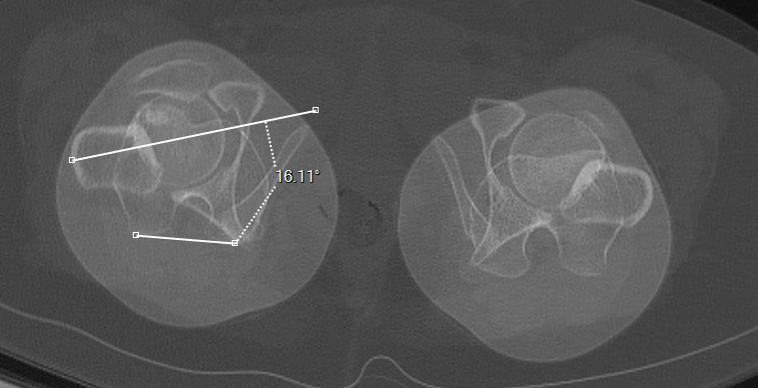

Torsion tibiale

D + F (plateau + malleol)

D

Plateaux tibiaux

F

Malléoles tibiales